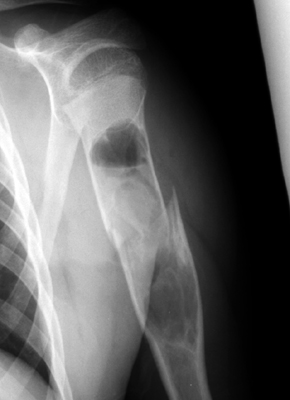

Diagnosis:Unicameral bone cyst Discussion:Two radiographs of a pathologic fracture in a simple bone cyst of the proximal humerus. Within the cyst is noted a small, thin, linear bony fragment which is displaced from the site of the fracture. An excellent sign of unicameral bone cyst. The fallen fragment secondary to pathologic fracture is pathognomonic for this cyst. A portion of the wall of the cyst has undergone a pathological fracture and subsequently floated down (fallen) via gravity into the dependent portion of the cyst. References: